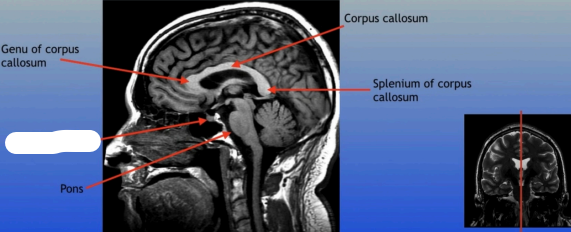

Genu of Corpus Callosum

The anterior part of the corpus callosum that connects the frontal lobes of the left and right hemispheres, playing a role in interhemispheric communication.

Pons

A round structure located above the medulla oblongata and below the midbrain, it acts as a relay station for signals between the cerebellum and cerebrum, and plays a role in regulating sleep and arousal.

Corpus Callosum

Splenium of Corpus Callosum